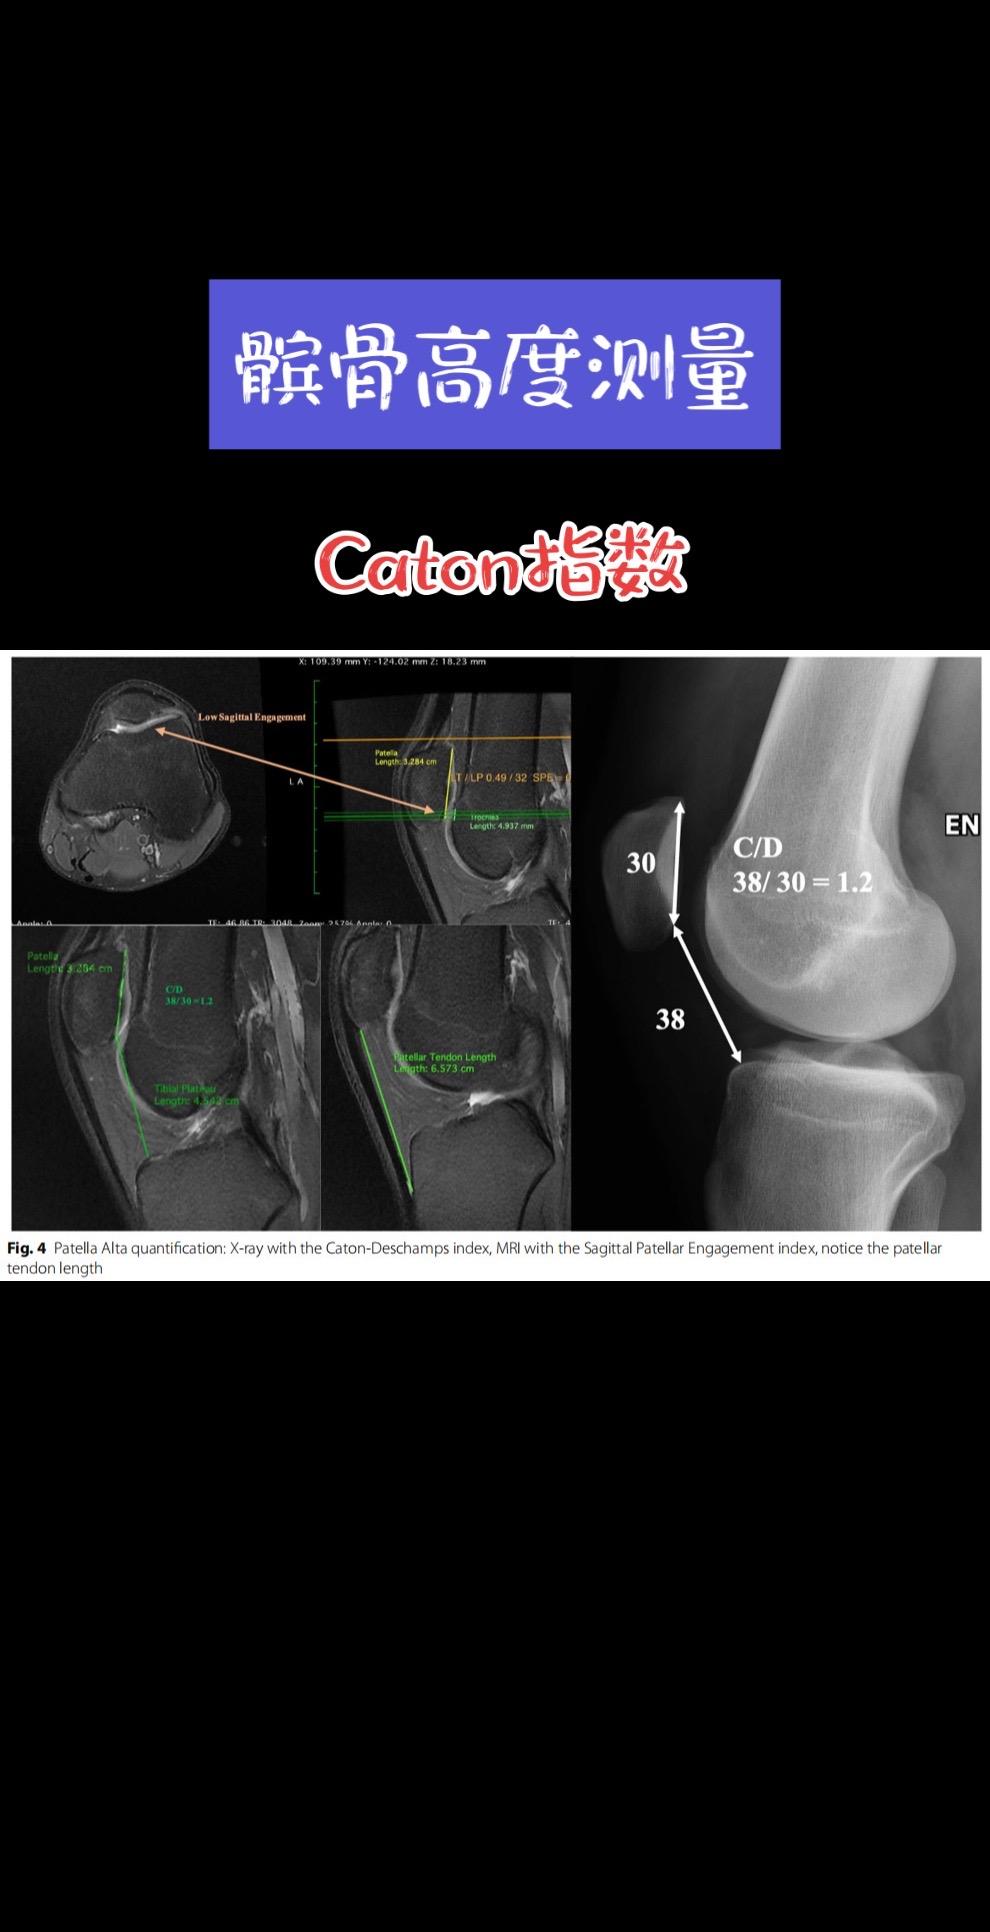

滑车发育不良Dejour分型。髌骨不稳的治疗需重点关注骨性解剖异常,其中滑车发育不良的评估在髌骨脱位的诊疗中具有关键意义。